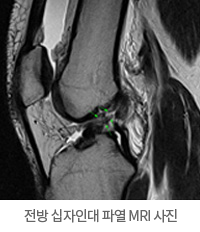

정형외과 전문의는 이학적 검사를 시행하게 되고, 십자 인대 파열이 의심되는 X-ray 검사 및 MRI 검사를 시행하게 됩니다.

MRI 검사는 전방 십자 인대 같은 연부 조직을 보기 위한 검사로 가장 유용한 검사입니다.

전방 십자인대 파열 MRI 사진